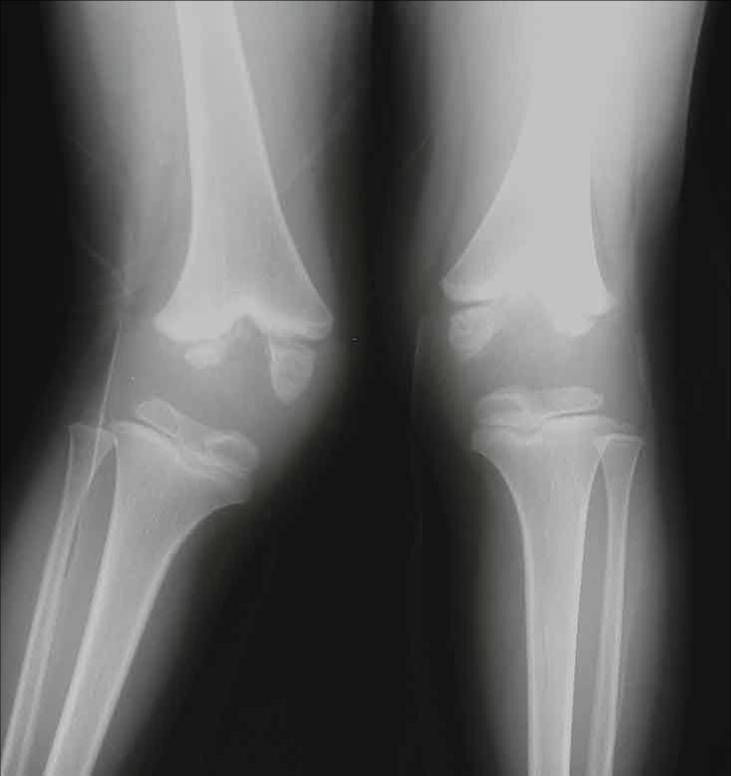

Permanent and irreversible joint damage (also known as hemophilic arthropathy) is the most common complication of hemophilia that leads to disability. It is caused by repeated bleeding into the same joint, and over time results in the destruction of the cartilage and synovium (the lining of the joint).